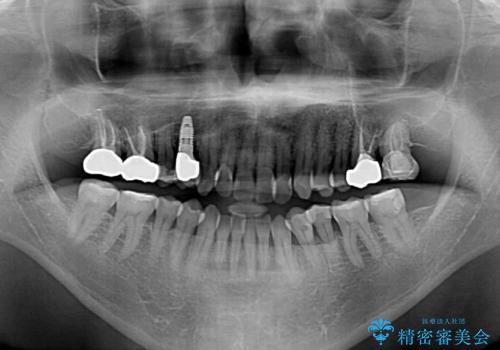

- 前歯のクロスバイトを気にして来院された患者様です。

40代男性で、インプラント補綴治療も経験されている方で、矯正治療をしても良いのかと悩んでいらっしゃいました。

下顎骨の左右のずれがあり、下顎全体が前方に出ている状態であったので、無理をせずにワイヤー装置にて矯正治療を行うこととしました。